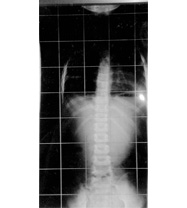

平成22年7月29日来院

正常範囲と診断 4歳9ヶ月

平成22年6月23日

正常範囲度数云われず

きれいな身体と肋骨変形も改善

レントゲンは正面からです

この期間治療は3ヶ月に一度、最終治療は平成22年2月が最後です。現在当院治療終了

(注)自宅で毎日RHPl木型を使用、体幹を無理なく伸ばし、よい装具で保護する方法。